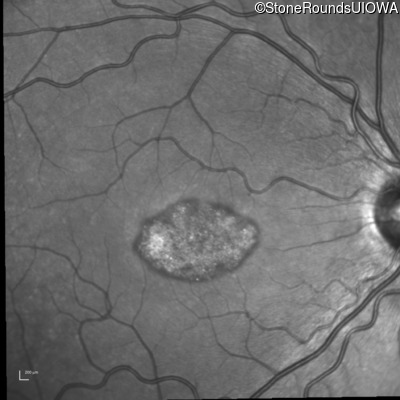

This 22 year old man had macular abnormalities noted incidentally at a routine eye exam at age 19. Since then, he has experienced a gradual loss of acuity particularly in the left eye.